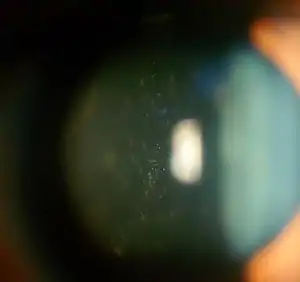

| Anterior vitreous cells in Intermediate uveitis | |